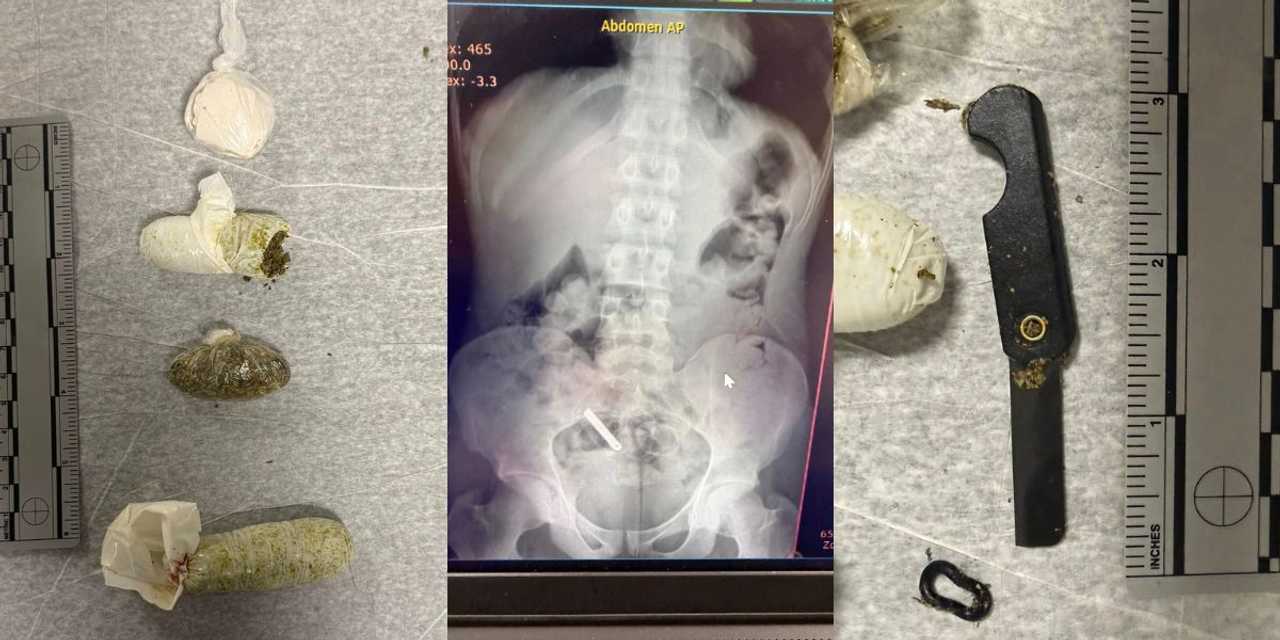

Corrections officers at the Albany County Jail found razors and drugs hidden inside an inmate’s body, according to sheriff’s officials.

Officers seized two razors and marijuana, despite efforts to conceal the items inside the inmate’s body, Sheriff Craig Apple said.

Photos shared with the post showed the contraband packaged in plastic baggies and an x-ray, the blades clearly visible near the inmate’s pelvis.